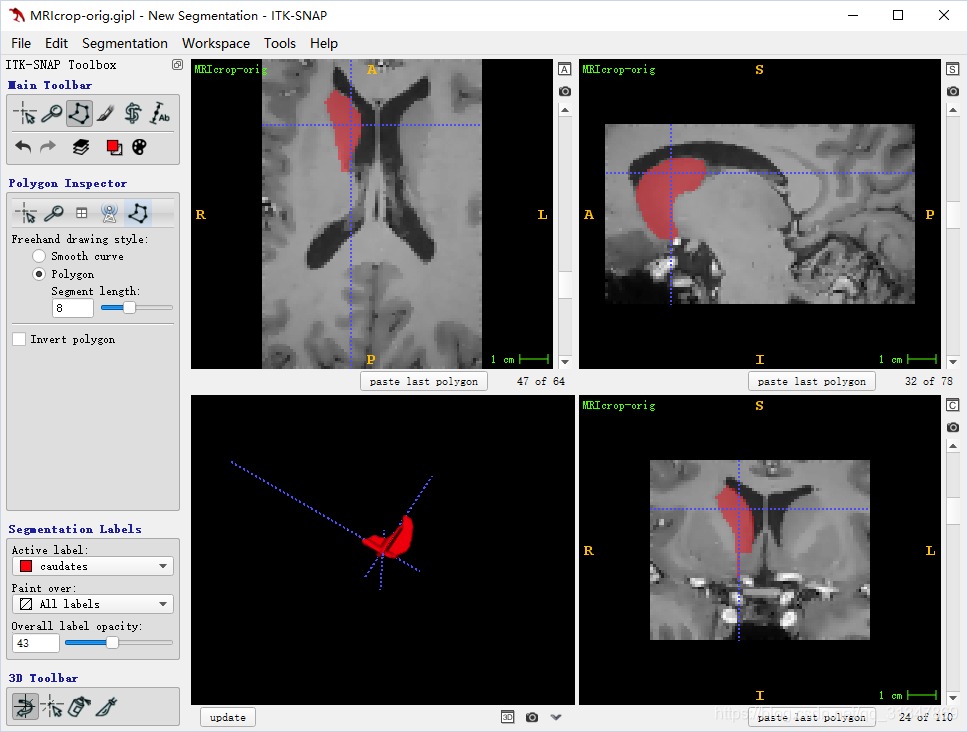

手动分割:

在 Active Label 下选择一个标签,然后基于此标签进行分割

Paint over 为 all labels,表示分配的标签将覆盖掉已经有标签的 voxels

选择 Polygon mode,左键单击绘制边界,注意最后一条关闭多边形的线会自动出现

视图下方可以 undo 或 clear 绘制的标签

分割好以后视图下方会变成:

此时在视图上手拉一个矩形框,可以选中所有分割的结点,拖动矩形框就可以移动分割的边框:

单独拖动某一个结点,也可以修正分割结果

修改好之后,点击 accept,多边形内会填充当前标签的颜色

注:记得将 Overall label opacity 调大一点,不然看不到标签

要清除标签的某一部分,可以将当前标签设置为 “Clear”,覆盖掉需要清除的标签即可。

SNAP 可以保存最近依次绘制的多边形,当在同一视图的不同切片上切换时,可以直接用 paste 复制多边形区域,然后做出微调即可。

在一个视图中绘制的多边形,在其他两个视图中表示为一条线。

在三个视图中都绘制好多边形区域,点击 3D 视图下的 update,就可以看到 3D 分割结构: